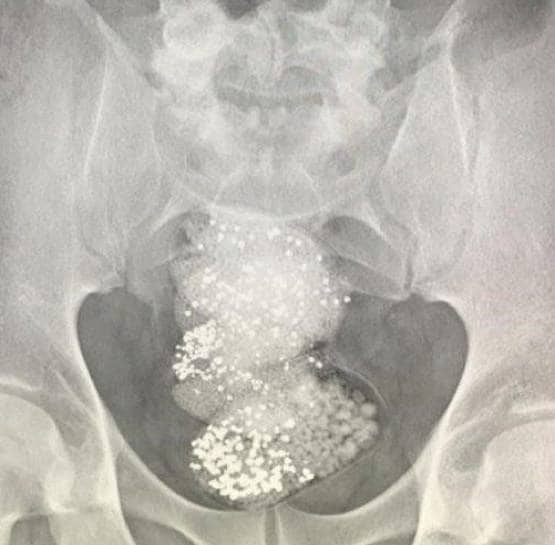

जब वह व्यक्ति जब शारजाह एयरपोर्ट पर पहुंचा, तो उसका पासपोर्ट जब्त कर लिया गया और उसके बैग की तलाशी ली गई, और फिर एक्स-रे हुआ. उसका इसके बाद जो हुआ उसे देख अधिकारियों के होश उड़ गए.

एक्स-रे करने के बाद अधिकारियों ने पाया कि यात्री ने 297 ग्राम कच्चे हीरे निगल लिए थे, जिनकी कीमत लगभग 90,000 डॉलर (64 लाख रुपये) थी.